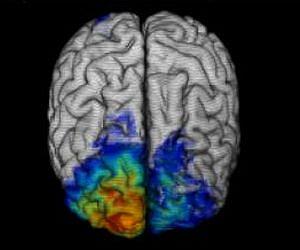

The image shows the overlap of lesions for eight subjects superimposed on a template brain - red indicates maximum overlap (seven subjects) and dark blue is minimum overlap (one subject). The patient group was selected for lesions that include frontopolar cortex, but the lesions almost invariably extended outside to other parts of anterior prefrontal cortex. Credit: Christopher Kovach, University of Iowa.